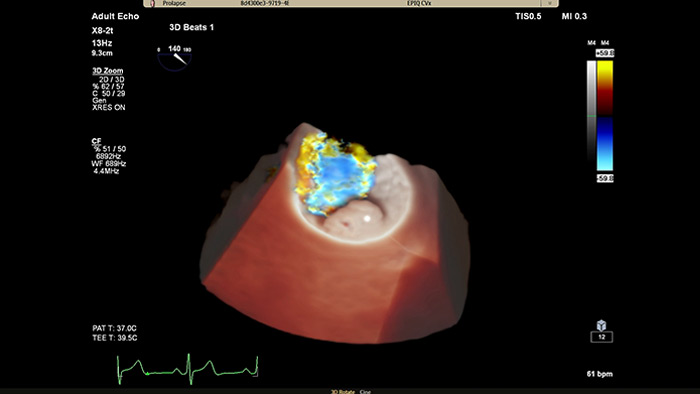

EPIQ CVx - TrueVue Color

View enhanced visualizations of structures and flow with TrueVue Color

• Better appreciate structural heart abnormalities and impacted blood flows to perform the correct procedure with confidence